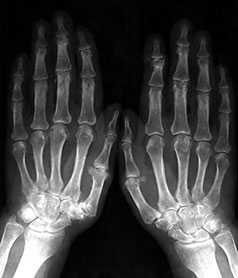

Выраженные изменения (соответствуют 3–4 стадиям артроза по Kellgren):

Умеренно выраженные или крупные остеофиты, деформация краев суставных поверхностей, значительное сужение суставных щелей, остеосклероз (узелки Гебердена в дистальных межфаланговых суставах и узелки Бушара в проксимальных), кисты со склеротическим ободком, краевые дефекты суставных поверхностей, при этом костные выступы с одной стороны могут вклиниваться в другую. Обычно краевые дефекты окружены зоной остеосклероза (рис. 3).

Рис. 3. Обзорная Rо-графия кистей.

Множественные артрозы дистальных и проксимальных межфаланговых суставов. Множественные узелки Гебердена и Бушара. Выраженный артроз 1-го левого запястнопястного сустава